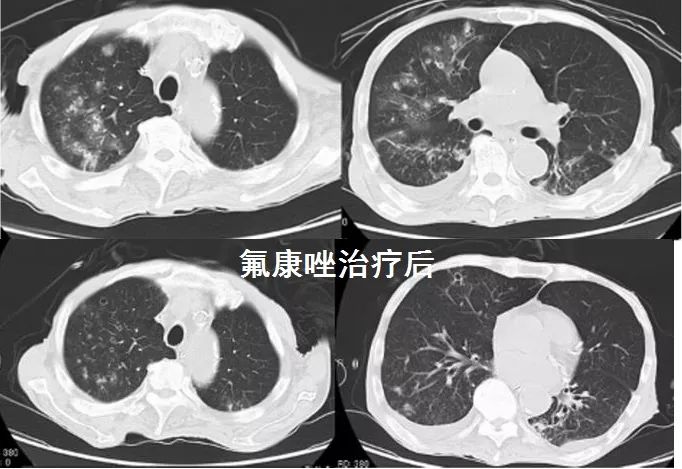

下面是1例病理确诊的,CT无特异。[1]

图1

下面是另外1例,临床诊断,单独氟康唑治疗好转,CT示多发空洞,肺念珠菌病空洞少见,算是一例不太典型的CT。[2]

图2